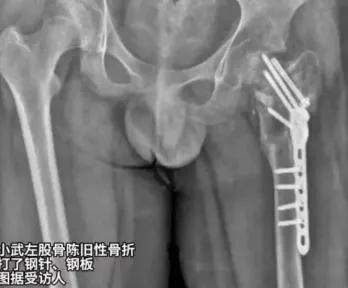

妈,我对不起你……病床上,14岁的小武左腿萎缩成细棍,右腿因长期肿胀如桶。这一切,只因他曾被母亲送进泉州一家号称专治叛逆网瘾的四维成长基地。 可那里哪是学校?分明是少年炼狱!28天里,小武遭遇通宵罚站,跪举水盆,扇耳光,关小黑屋,甚至被踢断腿后,反被诬陷装病,最终延误治疗致股骨头坏死,落下半残疾。更撕裂人心的是,基地竟逼哥哥动手打弟弟,让亲情在暴力下扭曲。 而这家机构的负责人向明胜,竟用民政局登记的公益牌子作掩护,实际干的却是虐待勾当。事发后,基地仍持续招生,直到孩子重伤,母亲二次报警,黑幕才被揭开。2025年9月,向明胜等4人因故意伤害罪,虐待被监护,看护人罪被诉,案件正待宣判。 多少家长,因焦虑把孩子推进火坑?多少矫正机构,正借爱之名行虐?小武的伤,大武的恨,是血的警示!暴力从不是教育,而是犯罪!唯有健全监管,破除矫治迷思,才能避免下一个孩子倒在为你好的棍棒下。